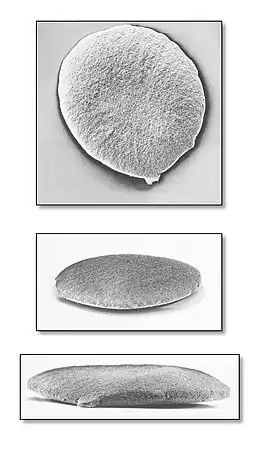

Chez le nouveau-né

- Conjonctivite (prévenue par usage de collyre au nitrate d'argent en systématique)